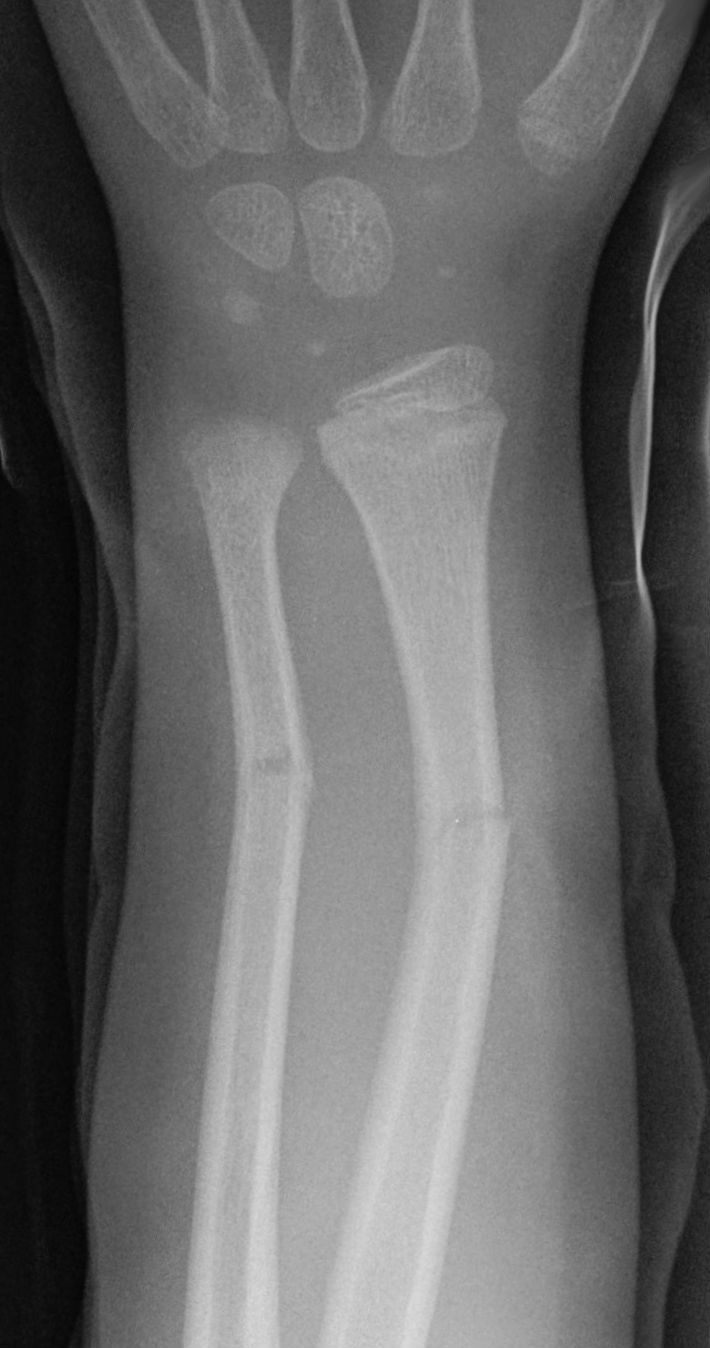

What is going on in this hand/wrist x-ray?

Taurus fracture or Buckle fracture

Common in kids and adolescents where the periosteum is stronger than the bone. More than half of these fractures involve the metaphysis only.

Any cortical “bump” should be considered a Taurus fracture if the kid has symptoms at the site.

Tx for nondisplaced fractures: splint of < 48 hours old, cast for 2-4 weeks if > 48 hours old. Repeat radiography is not indicated if symptoms improve.